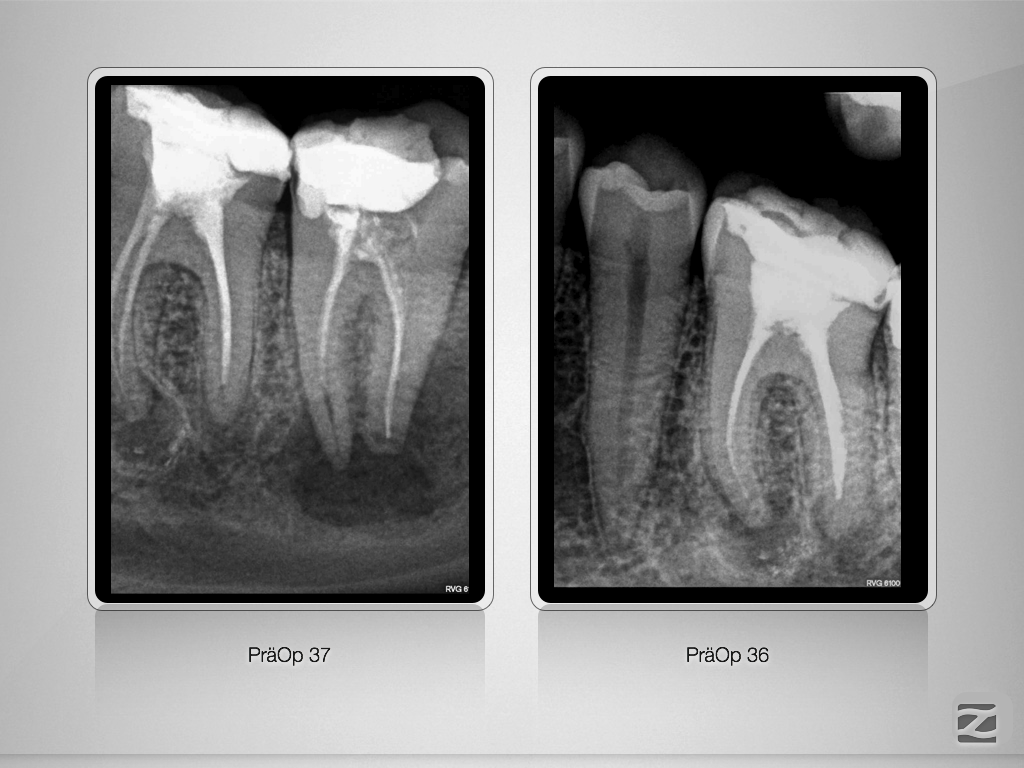

37D.001

Ausgedehnte apikale Lyse